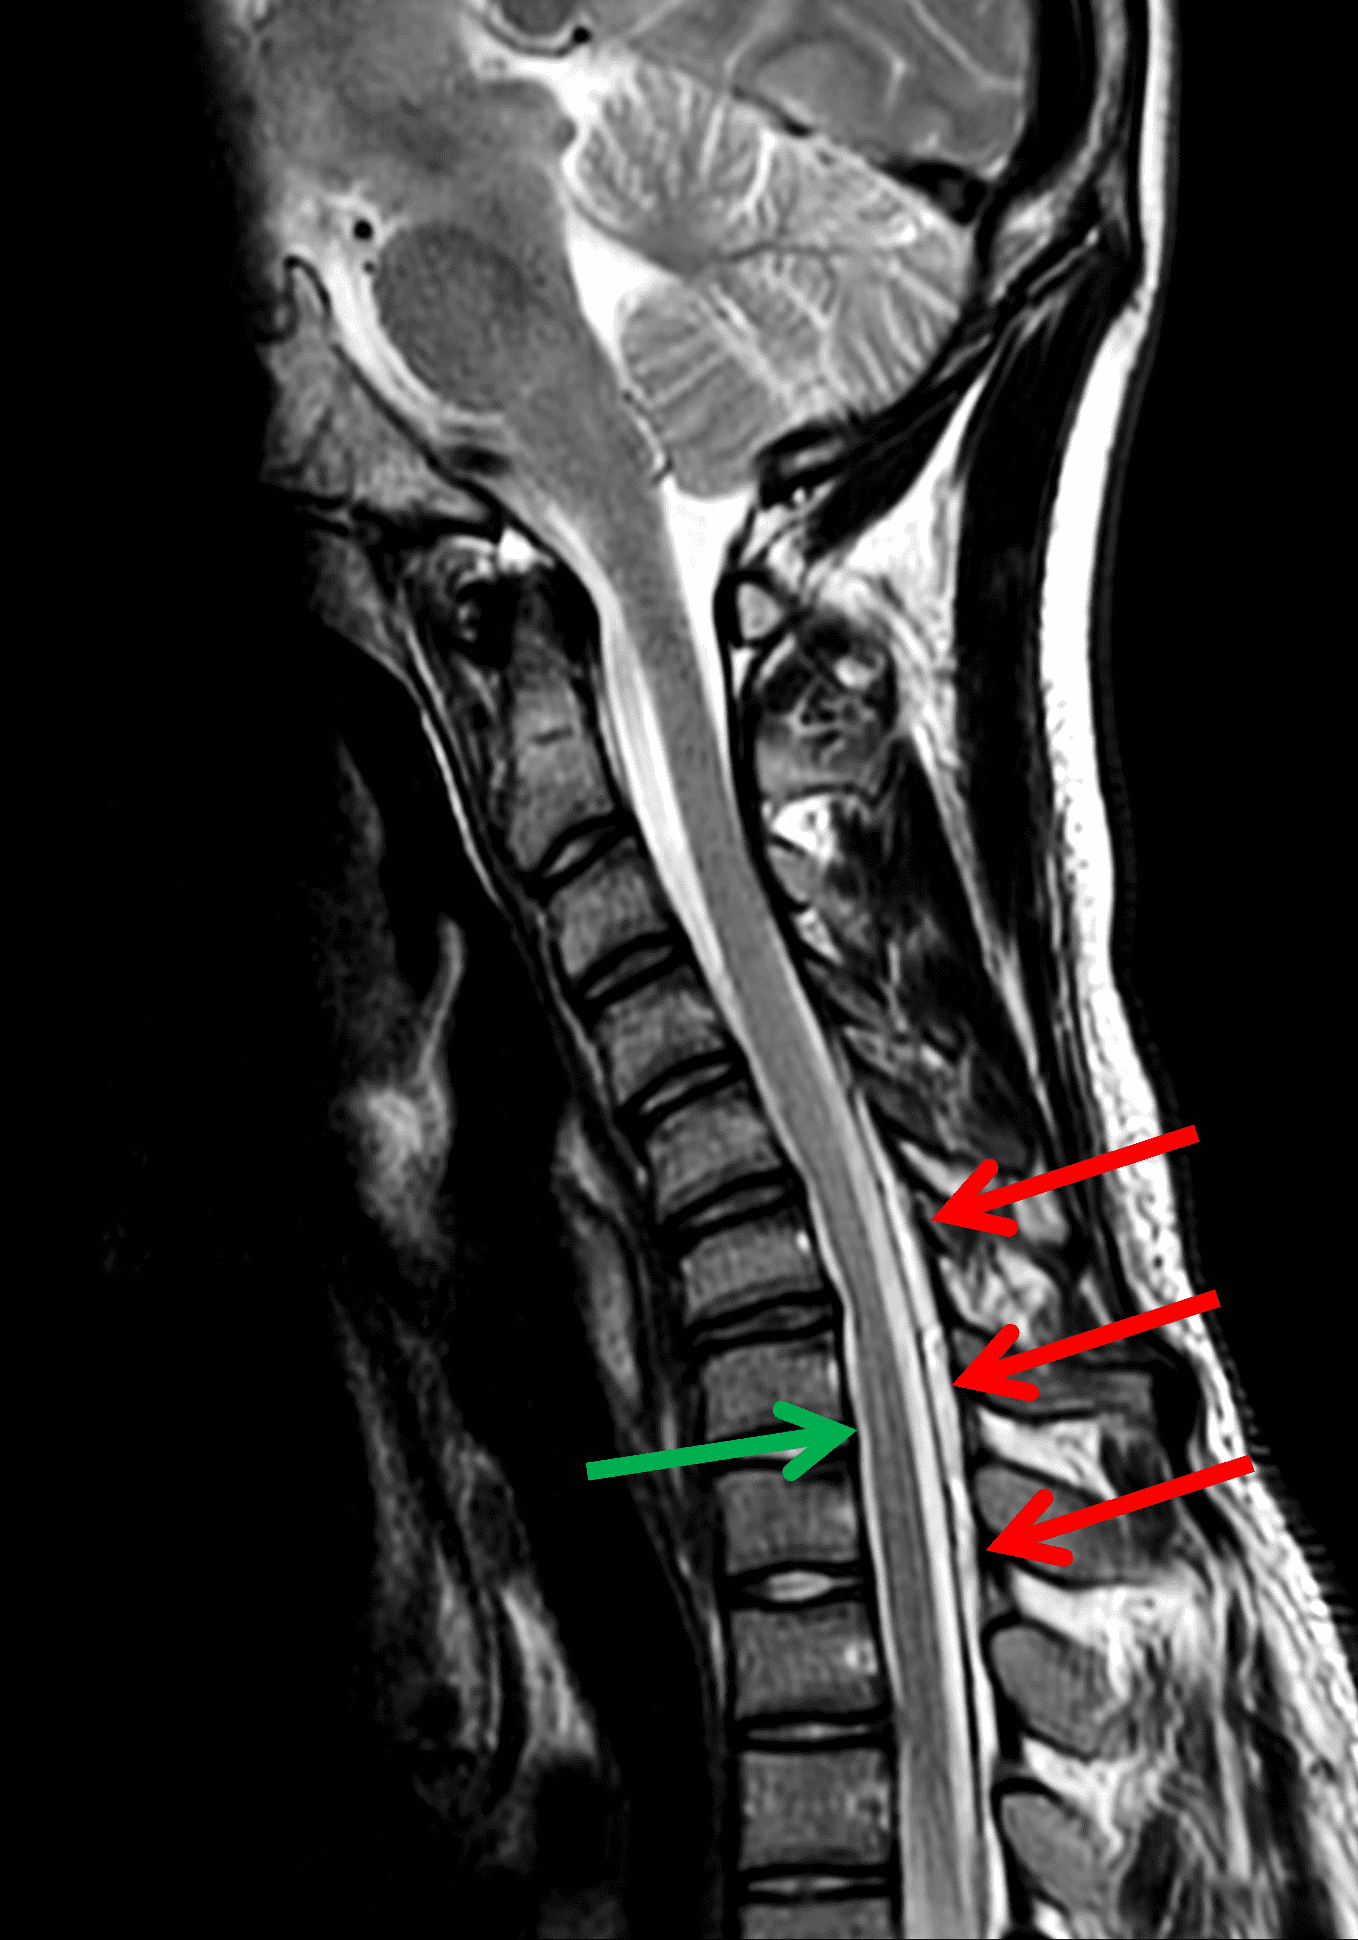

Figure 2: Neutral images of the cervical spine. Sagittal (2A) T2-weighted, (2B) T1-weighted, and (2C) STIR images show mild kyphosis, an enlarged posterior epidural space with loss of attachment of the dura (red arrows), and cord atrophy at the C6 level (yellow arrow). Subtle cord hyperintensity on the water sensitive images at the C7 level (green arrows) likely represents gliosis. (2D) Axial T2-weighted image shows enlargement of the posterior epidural space, right greater than left (red arrows). (2E) Axial T1-weighted image shows an enlarged posterior epidural space (red arrows) and cord atrophy, more severe on the right (yellow arrow).

Loss of normal cervical lordosis with straight or kyphotic curvature is a nonspecific but common finding in HD.8,19,29 By definition, normal lordotic curvature is curvature where no part of the dorsal aspect of C3 through C6 vertebral bodies crosses a line drawn from the dorsocaudal aspect of the C2 vertebral body to the dorsocaudal aspect of the C7 vertebral body (Figure 5), based on the principles of Guigui et al.30 and Batzdorf et al.31 Abnormal curvature of the cervical spine demonstrates a sensitivity of 82.6% and specificity of 47.1%.29

Figure 5: Sagittal T2-weighted image of the HD patient in Figure 1 shows loss of normal cervical lordosis (kyphosis). The red line extends from the dorsocaudal C2 vertebral body to the dorsocaudal C7 vertebral body. The C5, C6 and a small portion of C7 vertebral bodies cross posterior to the line.

The LOA sign was proposed as a finding suggesting HD on neutral position MRI of the cervical spine.29 The degree of loss of attachment of the posterior dural sac and subjacent lamina are evaluated on each side of the lamina at C4 to C6 levels on axial T2-weighted images, with separation along more than one-third of the lamina on one or both sides considered positive for LOA. To assess the degree of LOA, the lamina is defined medially by the point of junction of the lamina and laterally by a tangential line along the medial aspect of the pedicle and then divided into three equal parts (Figure 6). The LOA sign was found to have a sensitivity of 93.5% and specificity of 98% for HD. The LOA sign was investigated in the first multisite North American study by Lehman et al.5 and found to have a lower sensitivity of 70% but similar specificity of 100%. The authors confirmed that the LOA sign and other findings are often present on neutral position MRI and in the appropriate clinical scenario, should raise suspicion and prompt further assessment by flexion MRI to confirm the diagnosis.